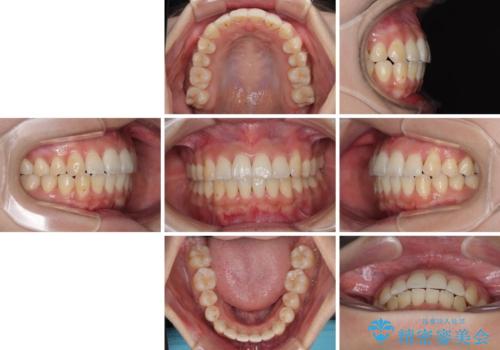

上顎の拡大は、左右どちらに拡大していくのか予想が困難ですが、こちらの患者様では結果として上下正中が一致する方向に拡大され、非常にきれいな仕上がりとなりました。

- 上下前歯のデコボコを気にして来院された患者様です。

上顎歯列が下顎の歯列に対して狭小であり、一部下顎の奥歯が上顎よりも外側に位置している状態でした。

上顎の急速拡大装置を使用して上顎骨を側方に拡大することで上顎歯列を拡大し、下顎歯列も拡大できるようにすることで、歯列を整えることとしました。